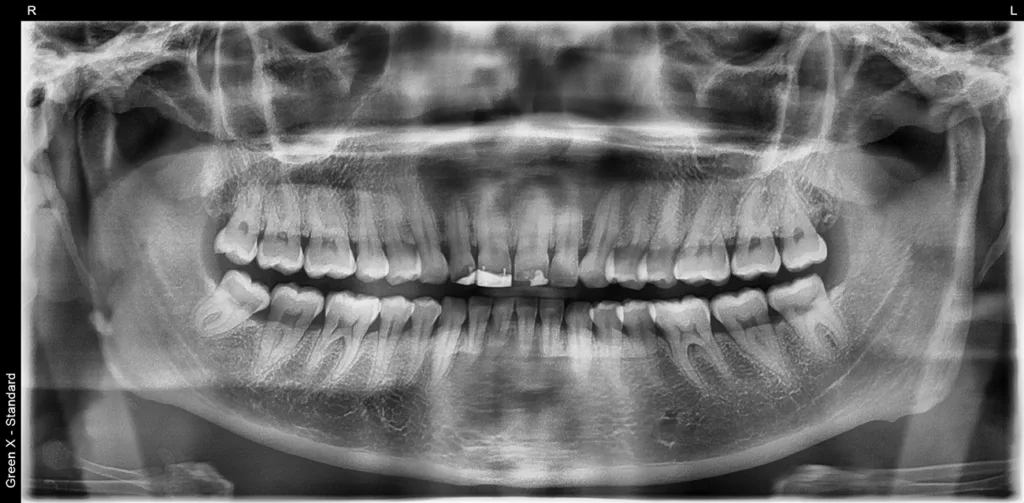

Darüber hinaus schimmerte die graue Farbe der Stifte durch den Kunststoff hindurch. Als Folge harmonierten die Inzisallinien der 4 Schneidezähne nicht mehr mit der unteren Lippenlinie. Vermutlich war eine unzureichende Frontzahnführung Ursache dafür, dass der Kunststoff wiederholt absplitterte und ein Inserieren von Stiften notwendig war, was damit ein dauerhaftes Problem darstellte. Die Patientin fühlte sich mit ihrem Lächeln sehr unwohl und suchte nach einer Behandlungsmöglichkeit, mit der ein ästhetisch ansprechenderes und natürlicheres Ergebnis erzielt werden konnte (Abb. 51 und 52).

Die ursprüngliche Planung sah vor, den alten Kunststoff und den Metallstift im Schneidezahnbereich behutsam zu entfernen, ohne dabei die gesunden Zähne zu beeinträchtigen. Beim Entfernen ging jedoch vor allem an Zahn 12 und 11 unerwartet viel Zahnsubstanz verloren. Dementsprechend musste die Behandlungsmethode angepasst werden. Ein bestmögliches Ergebnis versprach nach einer Zahnaufhellung die Versorgung der oberen Schneidezähne mit 4 Zirkoniumdioxidkronen.

Um die Zähne 21 und 22 so vital wie möglich zu erhalten, wurden sie rundum lediglich um ca. 1,5 mm reduziert. Bei den Zähnen 11 und 12 war dies vor allem inzisal nicht möglich, da sie nach der Entfernung des Metallstiftes und des Kunststoffes stark reduziert waren, jedoch nicht so stark, dass eine Wurzelbehandlung notwendig gewesen wäre. Die Zähne wurden anschließend mit neuen Kunststoffaufbauten versorgt und für monolithische Zirkoniumdioxidkronen präpariert. Während der provisorischen Versorgung wurden die Zähne regelmäßig kontrolliert, um den Erfolg der Restauration und das Ausbleiben von Komplikationen sicherzustellen (Abb. 53 bis 56).